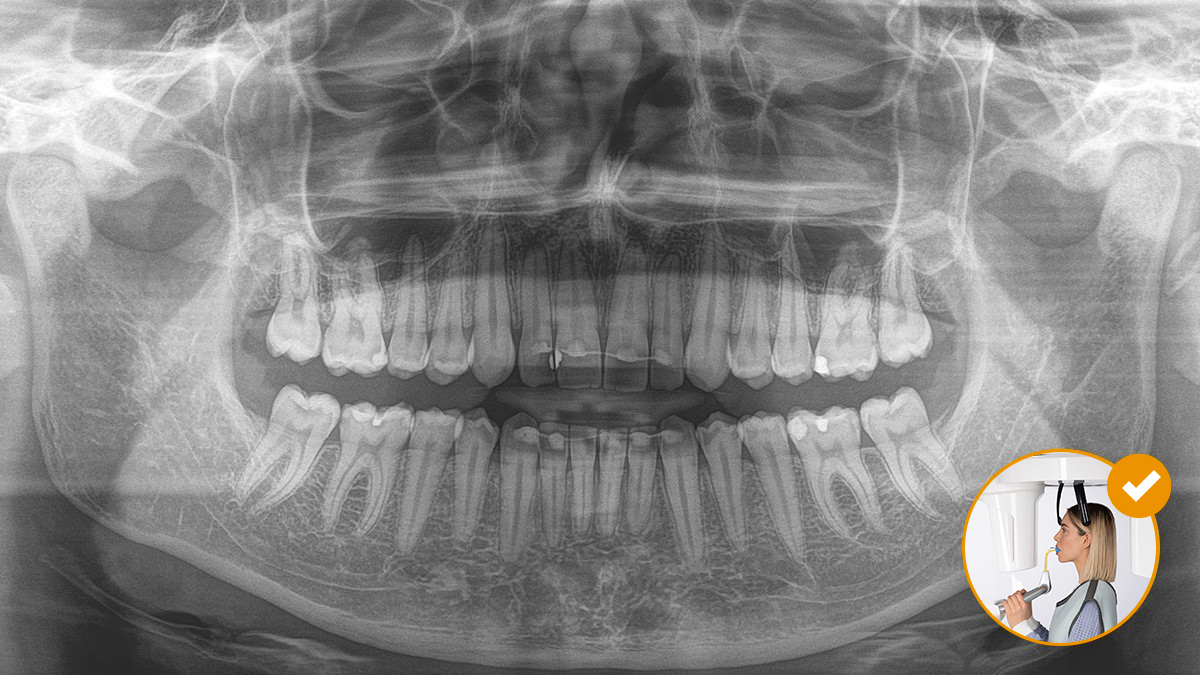

El posicionamiento correcto del paciente permite obtener imágenes de alta calidad que respaldan un diagnóstico preciso y facilitan y mejoran la experiencia del paciente.

Este es nuestro concepto de 10 puntos para facilitar el posicionamiento del paciente y la obtención de imágenes radiológicas. Se trata principalmente de dos cosas: alta calidad de imagen y comodidad para el paciente y el asistente.

El resultado: Escaneos precisos gracias al bloque de mordida oclusal